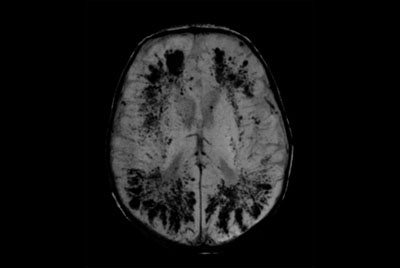

Alzheimer’s Disease Anti-Amyloid Immunotherapies (ARIA) 3.0T

Alzheimer’s Disease Anti-Amyloid Immunotherapies (ARIA) 1.5T